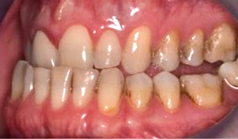

Fig 8. A class III adult male patient required surgical orthodontic treatment. The patient had anterior and posterior crossbites and required leveling of a deep curve of Spee during presurgical orthodontics.

Figure 8

Fig 9. A class III adult male patient required surgical orthodontic treatment. The patient had anterior and posterior crossbites and required leveling of a deep curve of Spee during presurgical orthodontics.

Figure 9

Fig 10. A class III adult male patient required surgical orthodontic treatment. The patient had anterior and posterior crossbites and required leveling of a deep curve of Spee during presurgical orthodontics.

Figure 10

Fig 11. Pretreatment lateral (Fig 11) and posteroanterior (Fig 12) cephalometric x-rays, along with a lateral overjet image (Fig 13). Maxillary deficiency was present in the transverse and sagittal planes.

Fig 13. Pretreatment lateral (Fig 11) and posteroanterior (Fig 12) cephalometric x-rays, along with a lateral overjet image (Fig 13). Maxillary deficiency was present in the transverse and sagittal planes.

Figure 13

Fig 18. Bite interdigitation to finalize surgical orthodontic correction. After orthodontics, periodontal plastic surgery, bleaching, microabrasion, and restorative dentistry were performed.

Figure 18

Fig 19. Bite interdigitation to finalize surgical orthodontic correction. After orthodontics, periodontal plastic surgery, bleaching, microabrasion, and restorative dentistry were performed.

Figure 19

Fig 20. Bite interdigitation to finalize surgical orthodontic correction. After orthodontics, periodontal plastic surgery, bleaching, microabrasion, and restorative dentistry were performed.

Figure 20

As previously mentioned, adult patients requiring orthognathic surgery often have esthetic dentistry and/or prosthodontic requirements. These are usually addressed after the surgical orthodontic correction has been completed and many times complemented through periodontal plastic surgery to improve the gingival architecture. A case report depicting this type of situation is presented in Figure 8 through Figure 20. In many instances the orthodontist is required to lead the interdisciplinary team and make appropriate coordinations with other dental specialties.1,11